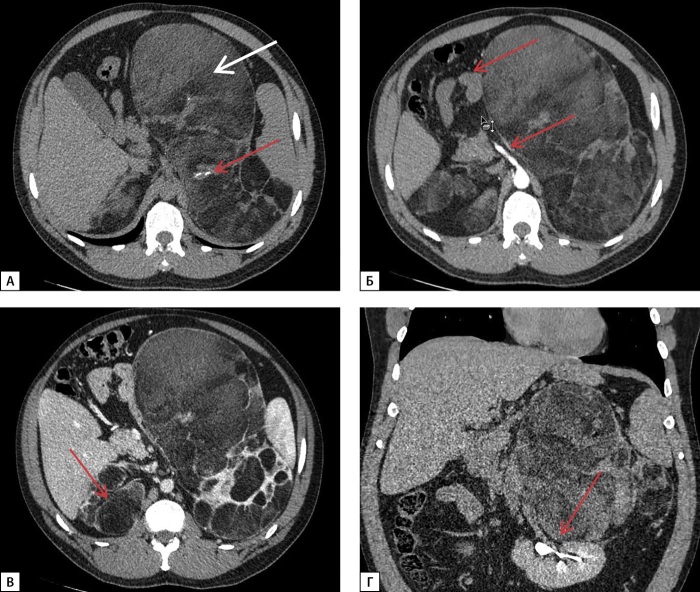

先天性肾上腺增生症(CAH)包括一组常染色体隐性遗传病,其特征是类固醇生成关键酶缺陷,其中CYP21A2基因突变导致的21-羟化酶缺乏症是最常见的形式。自从20世纪50年代引入替代疗法和新生儿筛查项目以来,诊断为CAH的新生儿的存活率显著增加。然而,尽管取得了这些进展,与这种疾病相关的死亡率仍然高得不成比例。通过药物治疗获得最佳治疗补偿仍然是一个复杂的挑战,导致一系列长期并发症。这些并发症源于潜在疾病及其治疗,影响关键的生理功能,包括代谢、生长发育、心血管健康和生育能力。这些多方面的结果强调了持续研究和改进治疗方法以更好地管理这一复杂疾病的必要性。这篇文章提出了一系列的四个临床病例CAH的特点是缺乏持续补偿糖和矿皮质激素缺乏。这些病例因大肾上腺肿块和异位睾丸肾上腺休息组织(TART)的发展而进一步复杂化,强调了实现长期疾病管理的挑战。

Congenital adrenal hyperplasia (CAH) encompasses a group of autosomal recessive disorders characterized by defects in enzymes critical for steroidogenesis, with 21-hydroxylase deficiency due to mutations in the CYP21A2 gene being the most prevalent form.Since the introduction of replacement therapy and neonatal screening programs in the 1950s, there has been a significant increase in survival rates among newborns diagnosed with CAH. However, despite these advancements, mortality associated with this condition remains disproportionately high. Achieving optimal therapeutic compensation through medication remains a complex challenge, contributing to a range of long-term complications. These complications stem from both the underlying disease and its treatment, impacting key physiological functions, including metabolism, growth and development, cardiovascular health, and fertility. These multifaceted outcomes underscore the need for ongoing research and the refinement of therapeutic approaches to better manage this intricate condition. This article presents a series of four clinical cases of CAH characterized by the absence of sustained compensation for glucoand mineralocorticoid deficiencies. These cases were further complicated by the development of large adrenal masses and ectopic testicular adrenal rest tissue (TART), emphasizing the challenges in achieving long-term disease management.